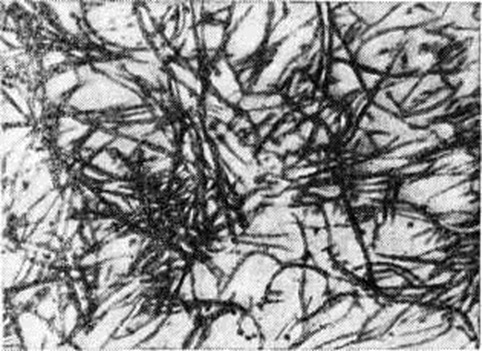

Гиалиноз относится к внеклеточным (мезенхимальным) диспротеинозам. Появление в цитоплазме гиалиновых капель (гиалиново-капельная дистрофия) или шаров (гиалиновые шары) не связано с Гиалиноз. Гиалин является фибриллярным белком (рисунок 1), в построении которого принимают участие плазменные белки, в частности фибрин. При иммуно-гистохимические исследовании в гиалине обнаруживают не только фибрин, но и компоненты иммунных комплексов (иммунные глобулины, фракции комплемента). Гиалиновые массы стойки к действию кислот, щелочей, ферментов, хорошо окрашиваются кислыми красками (эозин, кислый фуксин), пикрофуксином красятся в жёлтый или красный цвет; в массах гиалина могут откладываться липиды, соли кальция. Внешний вид органов и тканей при Гиалиноз зависит от стадии процесса; чаще Гиалиноз ничем не проявляется и обнаруживается лишь при микроскопическом исследовании. В тех случаях, когда процесс выражен резко, ткани становятся бледными, плотными, полупрозрачными. Гиалиноз, в частности артериол, может привести к деформации и сморщиванию органов (например, развитие артериолосклеротического нефроцирроза, клапанного порока сердца).

Гиалиноз наблюдается в соединительной ткани, строме органов и стенке сосудов (рисунок 2) в исходе плазматического пропитывания, фибриноидного набухания, склероза, хронический воспаления, некроза. В исходе плазматического пропитывания возникает Гиалиноз сосудов, чаще в артериальной системе. Наиболее распространён Гиалиноз мелких артерий и артериол (смотри Артериолосклероз). Гиалиноз артериол возникает в результате повреждения эндотелия, аргирофильных мембран и гладкомышечных волокон и пропитывания стенок сосуда белками плазмы крови, которые затем подвергаются ферментативным воздействиям, коагулируются и уплотняются, превращаясь в гиалиноподобное плотное вещество. Гиалиновые массы оттесняют кнаружи и разрушают эластическую пластинку, что ведёт к истончению средней оболочки; в результате артериолы превращаются в утолщённые плотные трубочки с резко суженным или полностью закрытым просветом. Гиалиноз мелких артерий и артериол, носящий системный характер, но наиболее выраженный в почках (рисунок 3 и 4), головном мозге, сетчатке глаза, поджелудочной железе, коже (рисунок 5), особенно характерен для гипертонической болезни (гипертонический артериологиалиноз). Нередко системный Гиалиноз артериол и мелких артерий наблюдается при хронический васкулярном гломерулонефрите и симптоматической артериальной гипертензии любого генеза. Распространённый Гиалиноз артерий эластического и эластическо-мышечного типов постоянно наблюдается при атеросклерозе, диабете и отражает процессы плазморрагии и инсудации, характерные для этих заболеваний. Местный Гиалиноз артерий как физиологическое явление встречается в селезёнке взрослых и пожилых людей, отражая функционально-морфологически особенности селезёнки как органа депонирования крови.